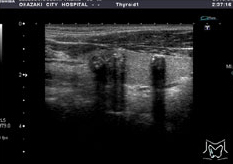

体表エコー

乳腺エコーでは全体を観察し、内部に「しこり(腫瘤)」はないか、乳腺組織が不均一になっているところはないかを調べます。甲状腺、耳下腺・顎下線も腫瘤性病変の発見や慢性疾患の観察を行います。体の表面にできた「しこり(腫瘤)」も同様に検査できます。